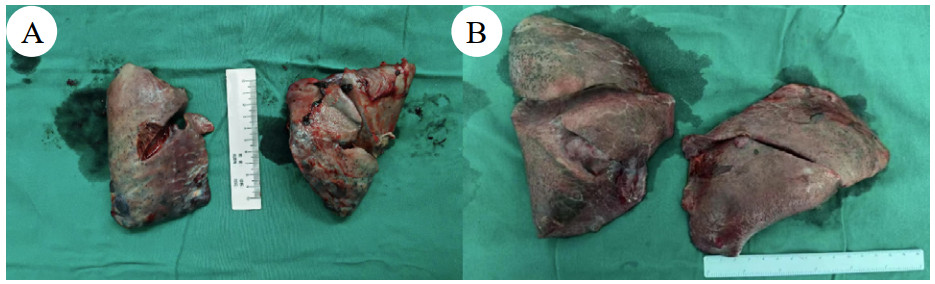

同时给予镇痛、镇静联合肌松,去甲肾上腺素泵入维持血压,俯卧位通气,B某入院后出现高热,经验性给予美罗培南联合万古霉素抗感染治疗,后降阶梯调整为哌拉西林他唑巴坦联合万古霉素治疗;C某抗感染方案为经验性使用万古霉素联合哌拉西林他唑巴坦治疗,痰培养出鲍曼不动杆菌后改为替加环素、头孢哌酮舒巴坦及万古霉素治疗;根据《刺激性气体中毒诊治专家共识》[5]中关于重症患者的治疗措施,同时给予2人泮托拉唑抑酸护胃,氨溴索、富露施化痰、甲泼尼龙抗炎、西维来司他纳及乌司他丁清除炎性介质,维生素C抗氧化、保肝、输血补液,纤支镜吸痰及肺泡灌洗,维持水电解质平衡及营养支持治疗,特别考虑到肺损伤情况,在使用有创通气时给予超保护性通气策略[5, 7];2人仍先后出现气胸、纵膈气肿,行胸腔闭式引流;持续V-V ECMO治疗15 d后,肺部纤维化不可逆转,高分辨率CT肺纤维化评分 > 75%(图 3、4),符合终末期肺病标准,有肺移植指征[8],经评估后2人顺利完成病变肺组织切除(图 5),双侧序贯肺移植,术后患者复查胸片肺部恢复正常(图 6),2位患者术后气管切管接呼吸机辅助通气,并给予泼尼松、他克莫司、吗替麦考酚酯抗排异治疗,其余根据病情给予万古霉素调节肠道菌群、抗感染、保肝、抗凝、呼吸康复锻炼等治疗,后顺利脱机、拔除气切套管,病情稳定出院,后续规律复查胸部CT(图 7)恢复良好。

| 注:图A为B某;图B为C某 图 5 患者病变肺组织 |

最终,对于此类毒性物质导致的终末期结构性肺损伤,进展为终末期肺病[11],肺移植成为了唯一有效的终极治疗手段[16]。本组病例的救治历程表明,急性重度有机氟中毒其临床进程可能远超常规ARDS,治疗窗口极为狭窄,多器官衰竭风险贯穿全程,需要临床医生在救治早期就具备前瞻性的判断和决策。